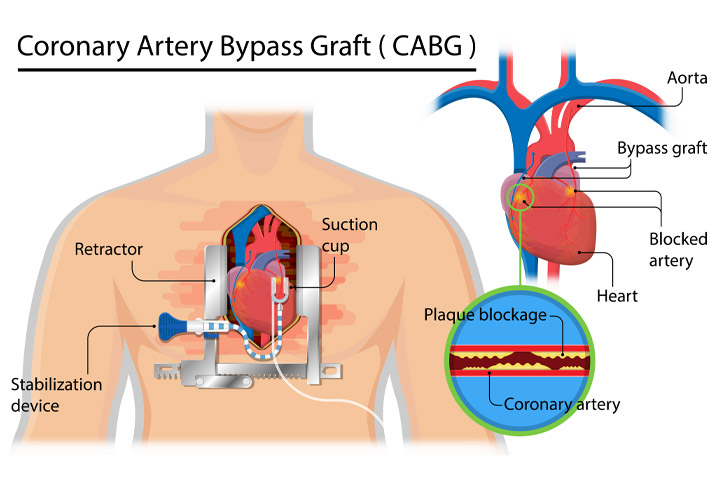

Overview

Package includes:

Days in hospital : 7 to 8 Days (For patient and one attendant)

Days in hotel : 12 Days (For patient and one attendant)

Room type in hospital : Shared

Room type in hotel : Private

Hotel category: Standard

Value added benefits of the CABG:

Ø Doctor consultation charges

Ø Lab tests and diagnostic charges

Ø Room charges inside hospital during the procedure

Ø Surgeon Fee

Ø Nursing charges

Ø Hospital surgery suite charges

Ø Anesthesia charges

Ø Routine medicines and routine consumables (bandages, dressings etc.)

Ø Food and Beverages inside hospital stay for patient and one attendant.

Extra benefits:

ü Interpreter

ü Visa assistance

Ø Site tourism of the city

Ø Follow up with the doctor

Ø Airport pick up and drop

Ø Free online consultation with the doctor

Ø Priority appointments with the doctor

Ø Room upgrade from sharing to private